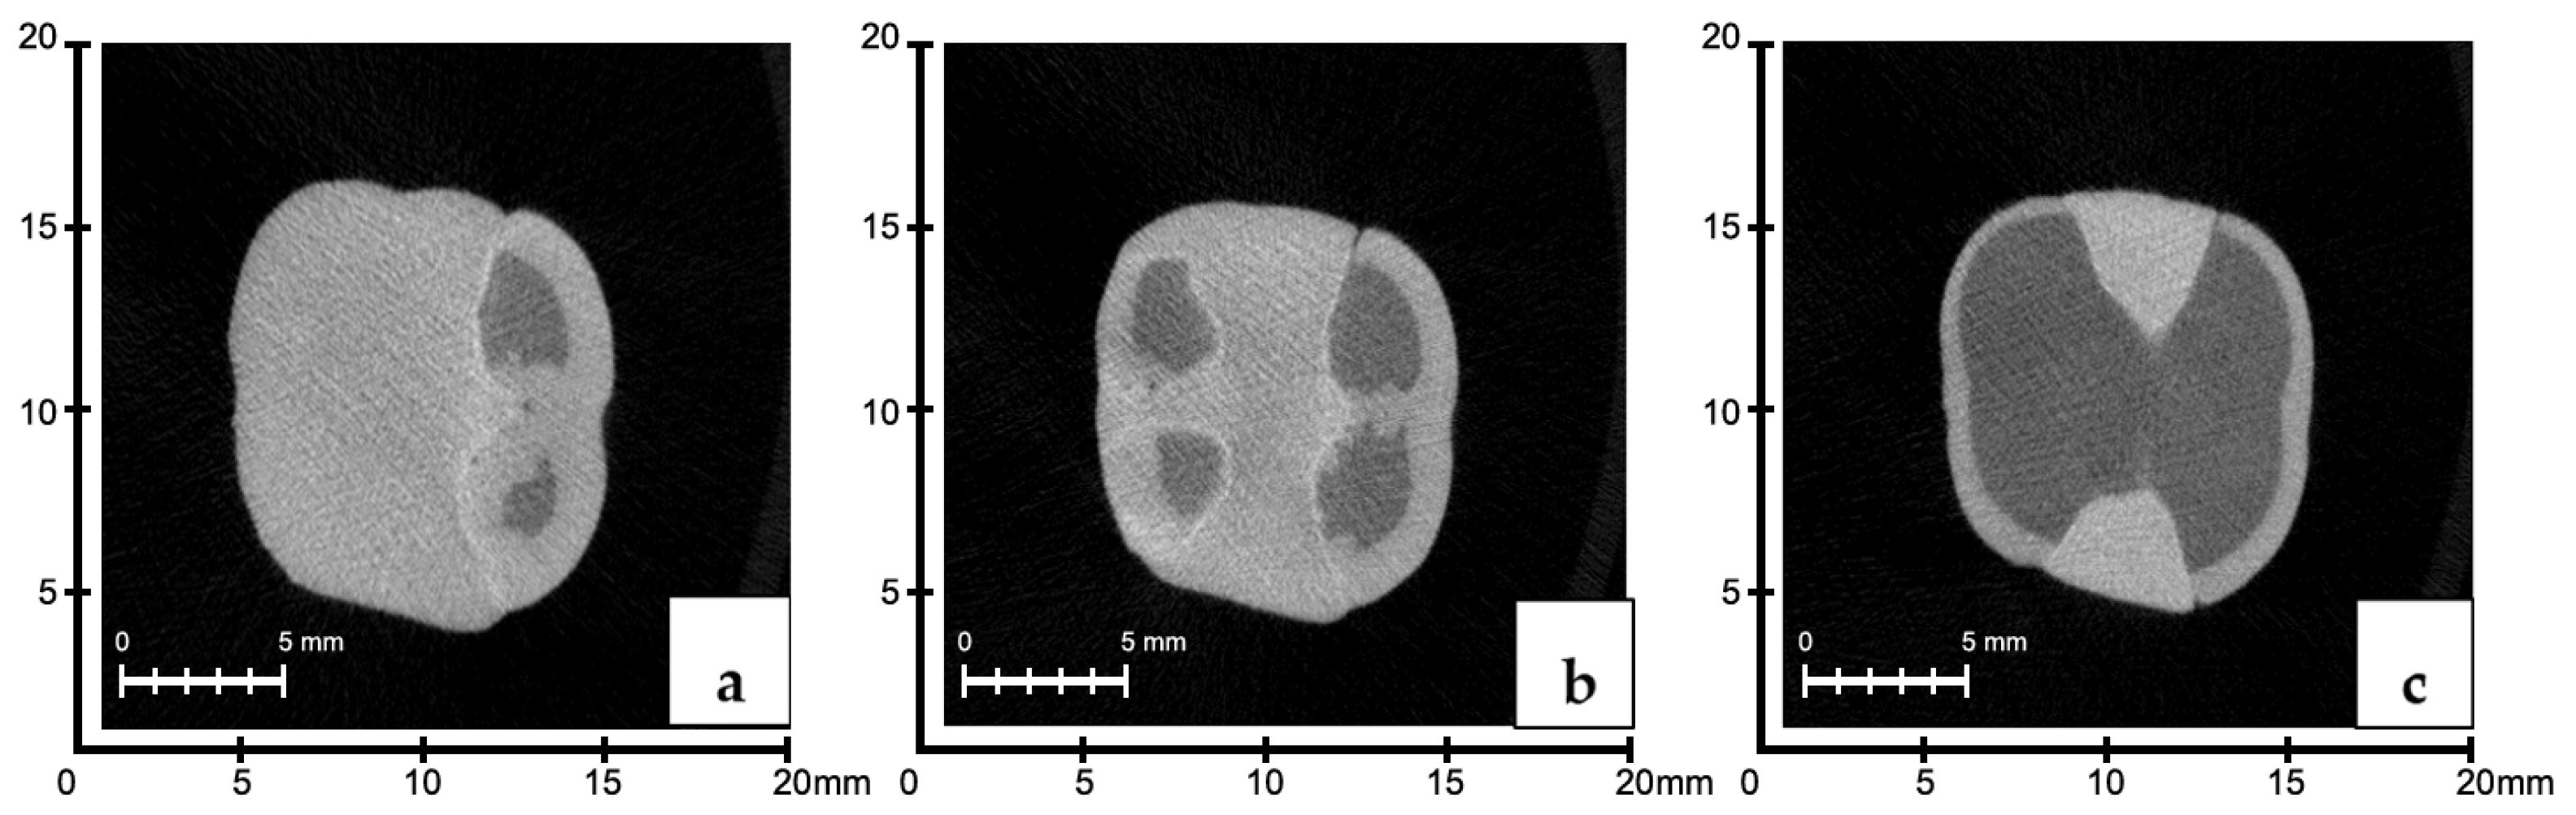

Measurement of Void Volume in the Restoration Material

3.3. Evaluation of Void Volumes in the Internal Structure of the Restoration According to Manufacturing Methods

3.4. Evaluation of Void Volume (mm3) in the Restoration Internal Structure According to Region

3.5. Evaluation of the BV/TV Ratios According to the Production Method and Region